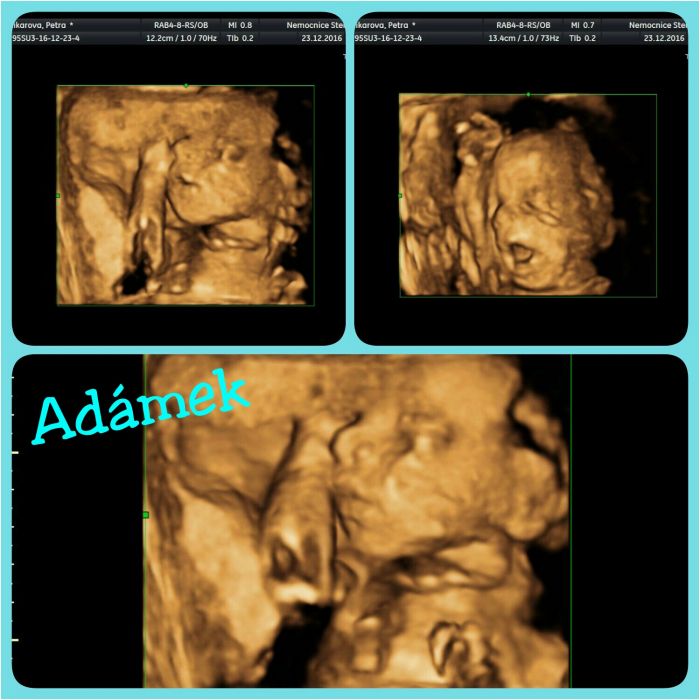

Luciku, to mate nadherny ten ultrazvuk, my fakt same strasidelne obrazky, na kterych musime hledat, kde co je. Ale tak zas tak o moc nejde.